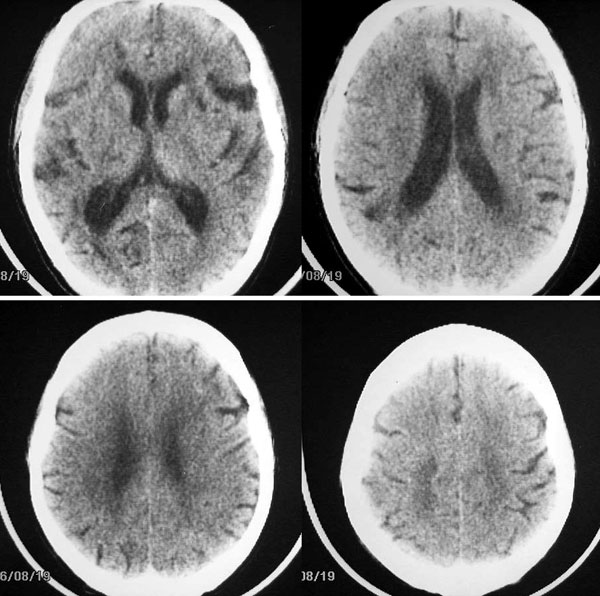

以下是引用卜一在2006-11-11 18:14:00的发言:[br]多发性腔梗,脑白质脱髓鞘变性,脑萎缩(老年性脑内三联征),考虑:皮层下动脉硬化性脑病.